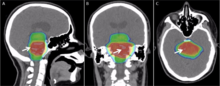

The planning of radiation therapy treatment has been revolutionized by the ability to delineate tumors and adjacent normal structures in three dimensions using specialized CT and/or MRI scanners and planning software.[59]

An enhancement of virtual simulation is 3-dimensional conformal radiation therapy (3DCRT), in which the profile of each radiation beam is shaped to fit the profile of the target from a beam's eye view (BEV) using a multileaf collimator (MLC) and a variable number of beams. When the treatment volume conforms to the shape of the tumor, the relative toxicity of radiation to the surrounding normal tissues is reduced, allowing a higher dose of radiation to be delivered to the tumor than conventional techniques would allow.[5]

Intensity-modulated radiation therapy (IMRT) is an advanced type of high-precision radiation that is the next generation of 3DCRT.[60] IMRT also improves the ability to conform the treatment volume to concave tumor shapes,[5] for example when the tumor is wrapped around a vulnerable structure such as the spinal cord or a major organ or blood vessel.[61] Computer-controlled x-ray accelerators distribute precise radiation doses to malignant tumors or specific areas within the tumor. The pattern of radiation delivery is determined using highly tailored computing applications to perform optimization and treatment simulation (Treatment Planning). The radiation dose is consistent with the 3-D shape of the tumor by controlling, or modulating, the radiation beam's intensity. The radiation dose intensity is elevated near the gross tumor volume while radiation among the neighboring normal tissues is decreased or avoided completely. This results in better tumor targeting, lessened side effects, and improved treatment outcomes than even 3DCRT.